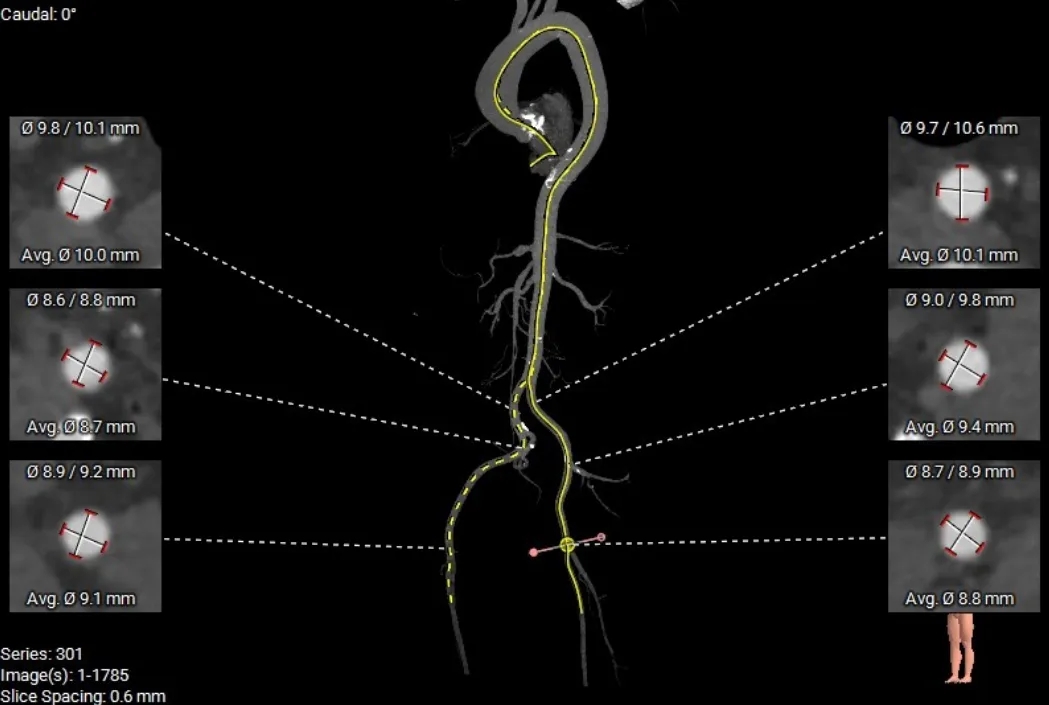

术前CT分析

主动脉根部测量

Annulus 20.7mm

LVOT 21.3mm

钙化积分 612

SOV

27.9*26.8*27.1mm

STJ 22.6mm

AAO 28.8mm

-

三叶瓣

流出道直筒型

重度钙化

STJ及升主无明显扩张

外周入路评估

双下肢内径尚可,髂动脉及腹主动脉可见钙化斑块,整体入路无明显迂曲。